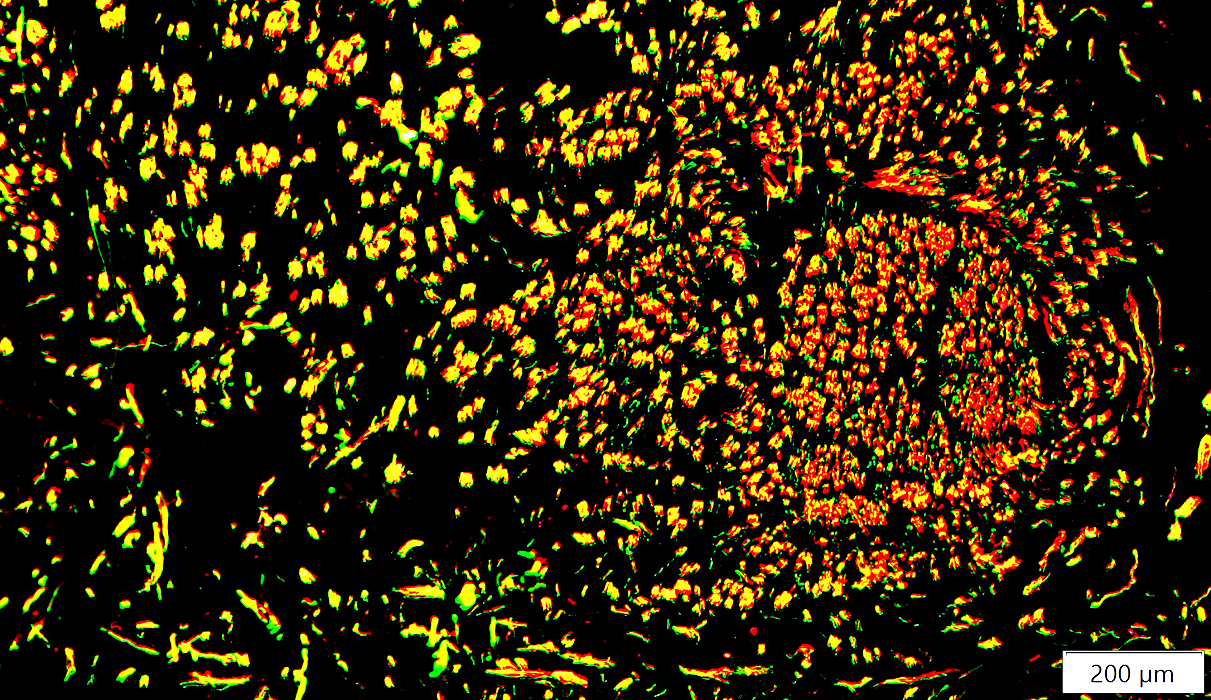

Neuroma: New Perineurial sheaths formed around small clusters of axons

P0(r).jpg)

EMA (Green): P0 (Red)

Perineurium in & around Neuroma

EMA (Green) stains scattered perineurial cells & rings of perineurium around small, aberrant regenerated axon (myelin) clusters (Red)

Compare to:

Nerve proximal to damage region

P0(r)b.jpg)